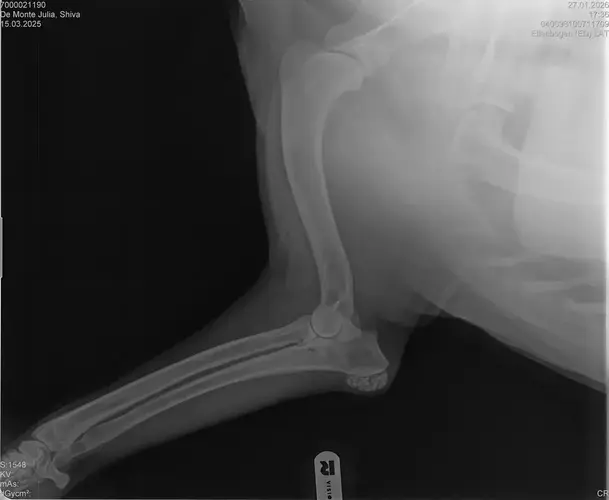

• Naja die Diagnose kommt von einem „Facharzt“, lt TA war ihrerseits alles i.O. Sie wollte noch sicher gehen und die Bilder zur weiteren Befundung einschicken und das kam dabei raus. Und der Therapievorschlag beläuft sich auf Ruhe, Ruhe und noch mehr Ruhe. Und einer Schmertherapie von Gabapentin 800mg 1/2 Tablette 2x tgl, Carprodyl 120mg 1 1/2 Tabletten 1x tgl und TamaCan CBD Tropfen 10-15 Tropfen 2x tgl. 1x in der Woche soll ich telefonisch Auskunft geben wie es Shiva geht. Das ganze mal für 14 Tage. Sie meinte noch sie hat viele Junghunde die ein Leben lang Schmerzmittel nehmem müssten. Die Röhrenknochenentzündung heilt in der Regel von selber der Rest gehört beobachtet… Ich weiß im Moment auch nocht so recht.. Er tut mir nur wahnsinnig leid mit sovielen Diagnosen und für mich war erstmal vorrangig ihn schmerzfrei zu bekommen. Das ist er inzwischen und versteht die Welt nicht mehr warum er nicht wie sonst spielen und arbeiten darf. Im Anhang noch Röntgenbilder falls sich jemand damit auskennt bzw Interesse hat..

• Ok, die Röntgenbilder sind aber auch extrem schlecht.

Panostitis ist idR sehr schmerzhaft, aber nicht unüblich und heilt in der Regel von alleine aus, wichtig dabei ist schonen und Entzündungshemmer zu geben, damit das nicht chronisch wird. Ich denke, dass die Akut bemerkbaren Schmerzen hauptsächlich davon kommen. Also da passt die Empfehlung deiner TÄ für's Erste auf jeden Fall.

Wenn dieser Panostitis-schub rum ist, würde ich dem Rest nochmal nachgehen. Man kann bei Dr. Tellhelm ( SV Gutachter) ein privatgutachten in Auftrag geben, das kostet um die 100€. Da kriegst du halt ne konkrete Einstufung und nicht "verdacht auf" und "könnte hiermit ODER damit in Verbindung stehen", etc.

Ich denke aber, dass du für ein Gutachten von Tellhelm nochmal neu röntgen lassen musst, ich finde, dass das Bild der Hüfte (HD und LÜW wird da beurteilt) und die Draufsicht auf die Ellenbogen (nötig zur Beurteilung von ED) unterirdisch sind!